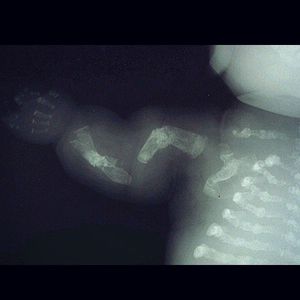

This is a lethal form of osteogenesis imperfecta (OI) in which the fractures even appear in utero, as revealed by this radiograph of a stillborn fetus. Note the irregular motheaten appearance of the long bones of the arm. The term "osteogenesis imperfecta" means imperfect bone formation. It is a congenital bone disorder characterized by brittle bones that are prone to fracture (often from mild trauma or with no apparent cause). Multiple fractures are common, and in severe cases, can occur even before birth (as seen in the mentioned case). People are born with defective connective tissue, or without the ability to make it, usually because of a deficiency of Type-I collagen. Diagnosed by occurrence of bone fractures with little trauma, and determining the quantity of type-I collagen. Treatment is aimed at increasing overall bone strength to prevent fracture and maintain mobility. Bisphosphonates can increase bone mass, and reduce bone pain and fracture.